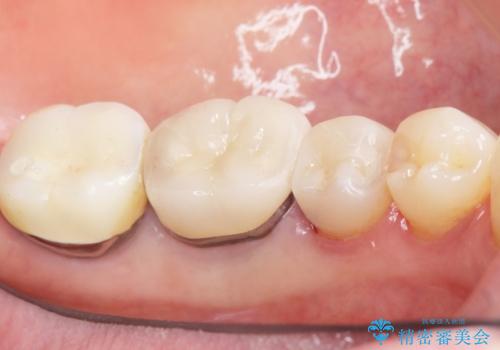

古い詰め物とう蝕を除去し、審美的で適合が良く二次う蝕になりにくいセラミックインレーによる修復を行いました。

審美的な仕上がりと自然な咬み心地に喜んで下さいました。

インレーの種類:セラミックインレー(e-max press)